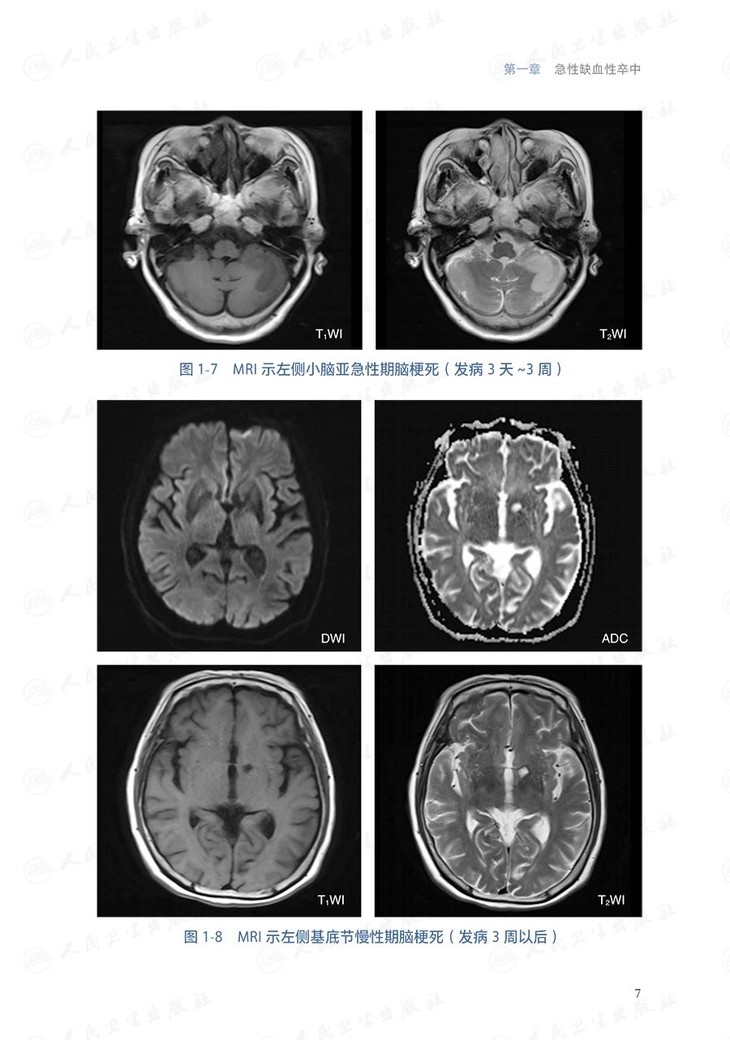

本分册共分12章,包括缺血性卒中、短暂性脑缺血发作、自发性颅内出血、蛛网膜下腔出血、 脑血管狭窄/闭塞、动脉瘤 、烟雾病、脑血管畸形、脑动静脉瘘、脑小血管病以及少见病因脑血管病。每个病种的撰写内容包括: 概述(包括定义和流行病学,简介病因与发病机制)、 临床表现、 辅助检查 (包括影像学检查等)、 诊断和鉴别诊断、治疗( 包括治疗前评估, 治疗方式选择, 治疗管理)以及预后评估及随访管理。对于从事神经系统疾病诊疗、教学及研究工作的神经内科、神经外科、神经介入科、急诊科、老年科等相关专业的医生、学生及研究人员具有较强的指导价值。